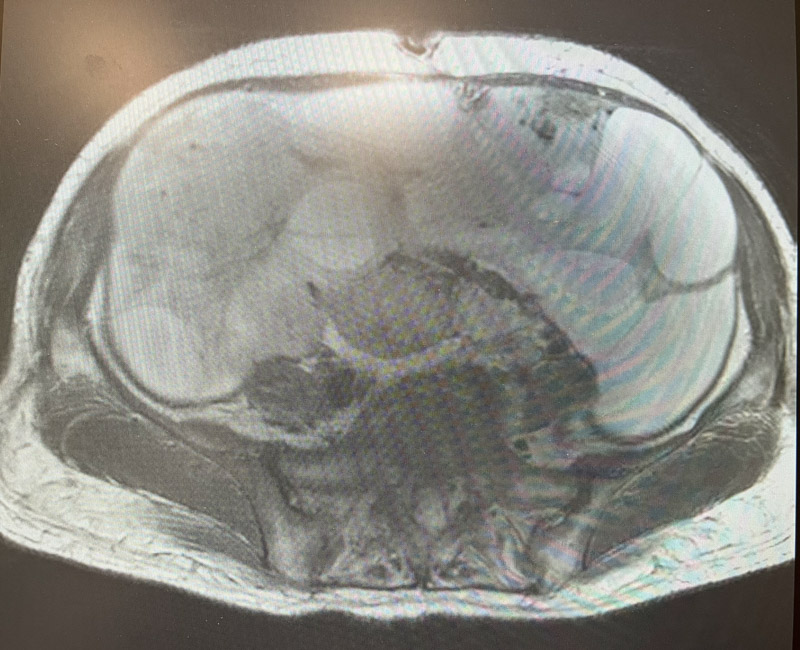

妇科二病区主任陈煜岊认真询问病史,并为患者进行专科检查。B超提示于盆腹腔见一186mm×117mm巨大囊实性肿物,上至剑突下,右至腋前线,左至腋中线。

经过详尽周密的术前评估及准备,在麻醉科的仔细的监护下,妇科手术团队开始进行手术,虽然已有心理准备,但看到腹腔内的巨大肿物还是让所有人感到震惊。手术过程中,进行的每一步都如履薄冰,手术医生凭借其精湛的技术以及对盆腔复杂解剖结构的精准把控,抽丝剥茧,一寸一寸推进,最终将巨大囊实性肿物取出体外,帮患者拆除了“炸弹”。